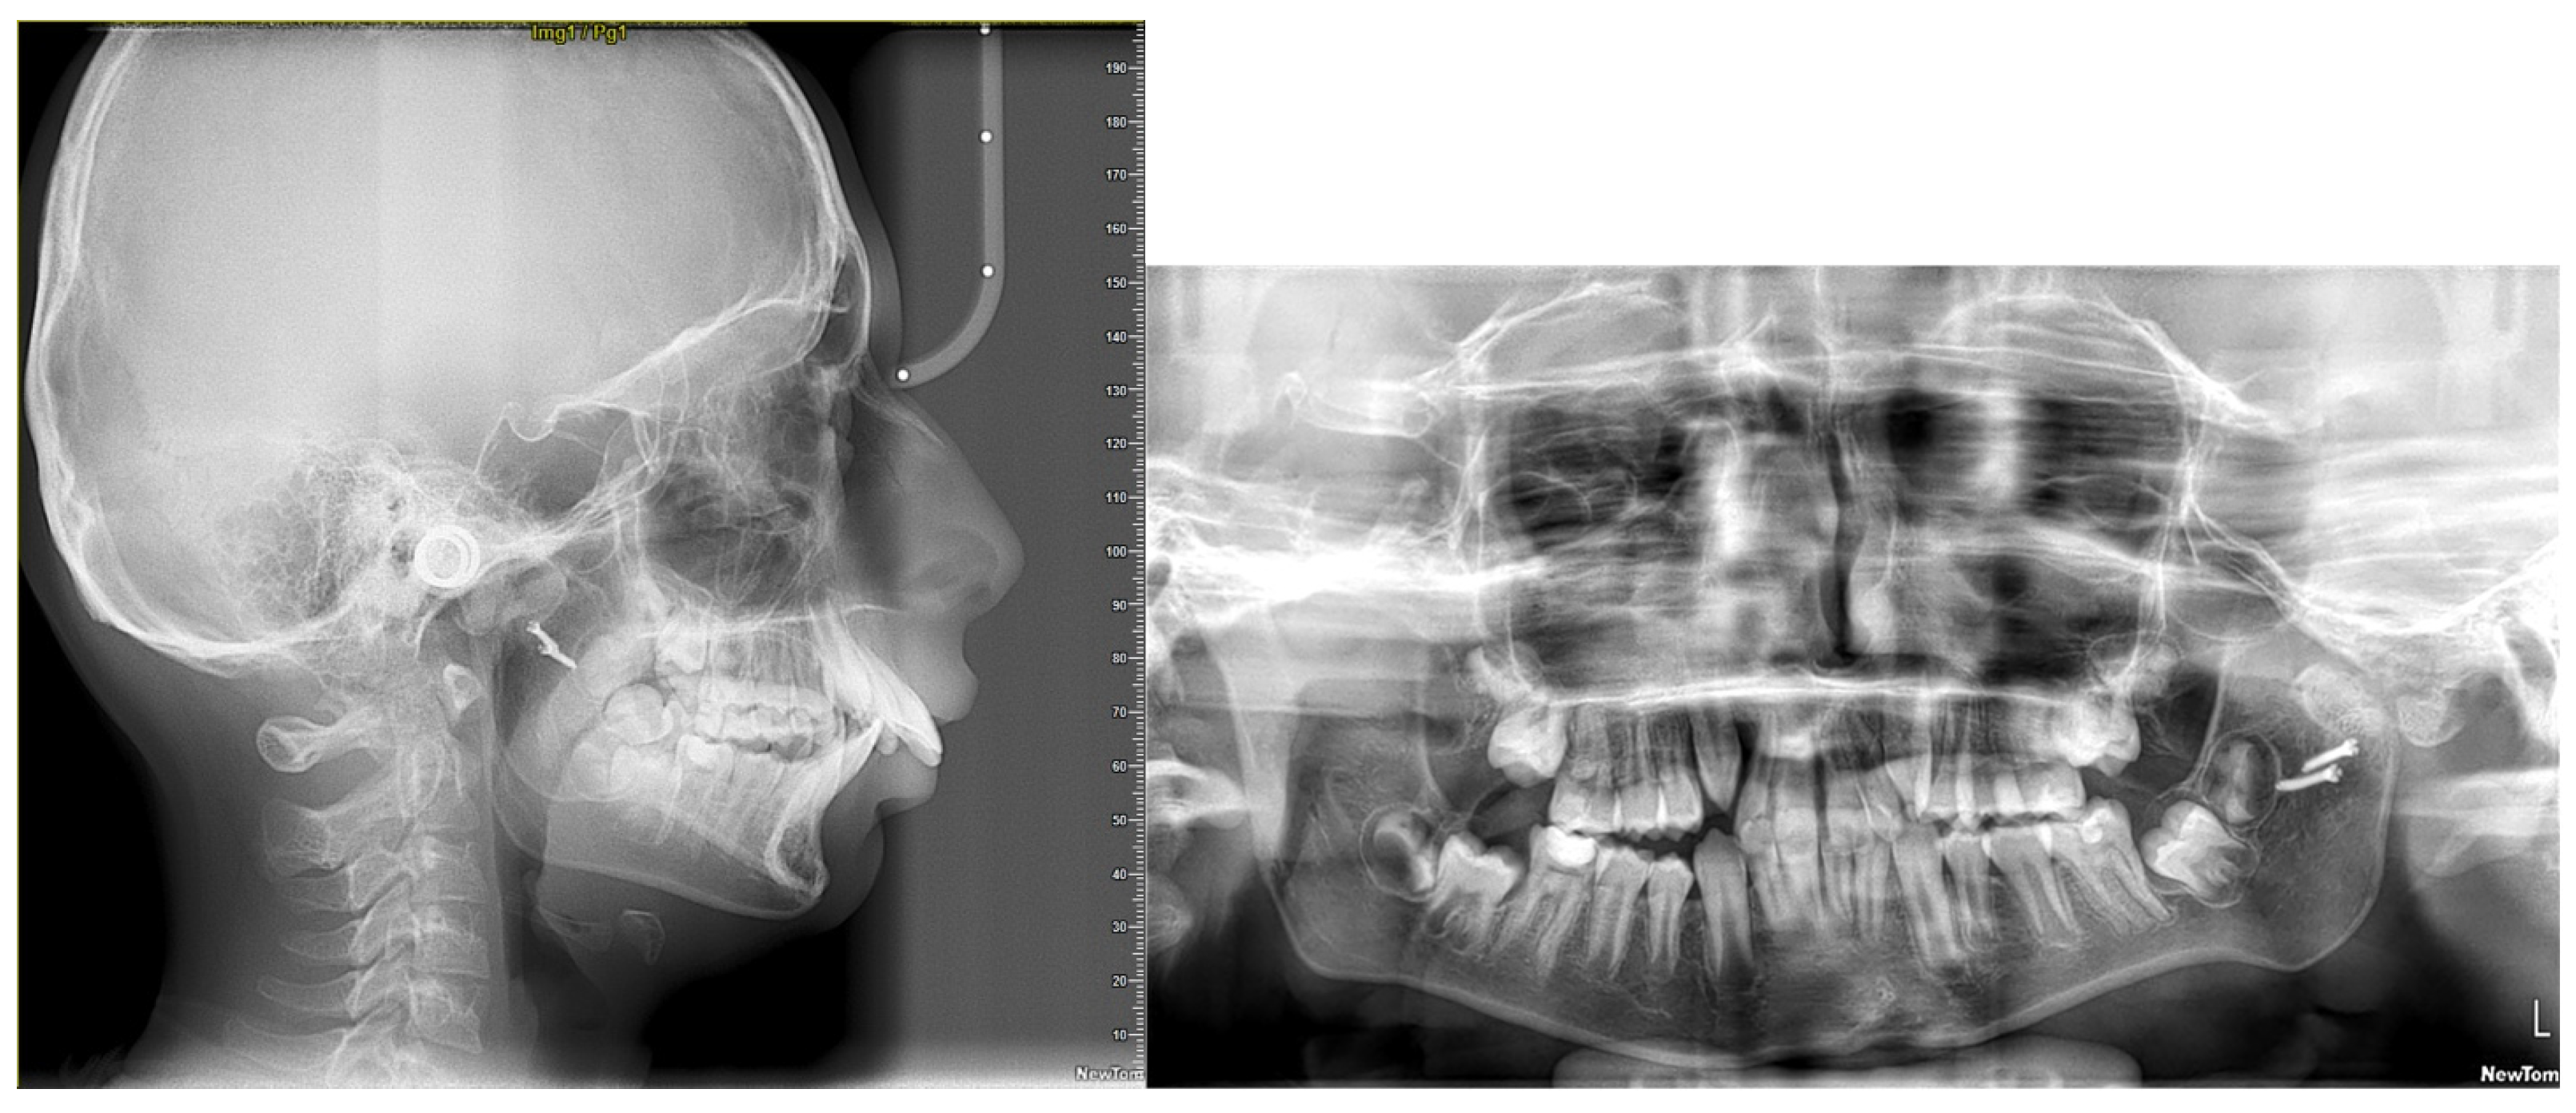

2. Diagnosis and Etiology

5. Treatment Progress